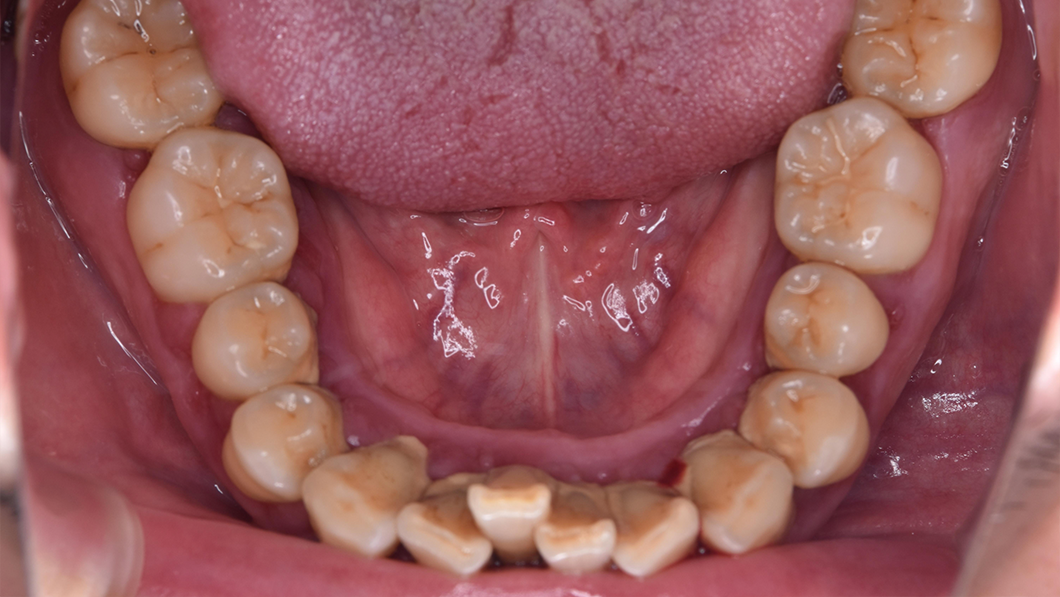

治療後

主訴 全額的歯周病による歯周組織の炎症

治療内容 SC、SRP、歯科衛生士実地指導、TCH指導